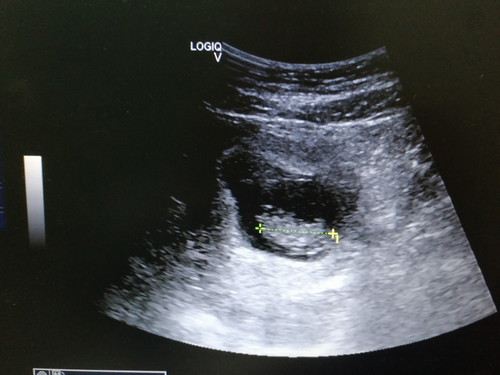

Precious ❤️

9 weeks 2 days ❤️ Nampak degupan jantung dia td.. Doakan baby & mummy sihat? And cepat2 la morning sickness hilang ?